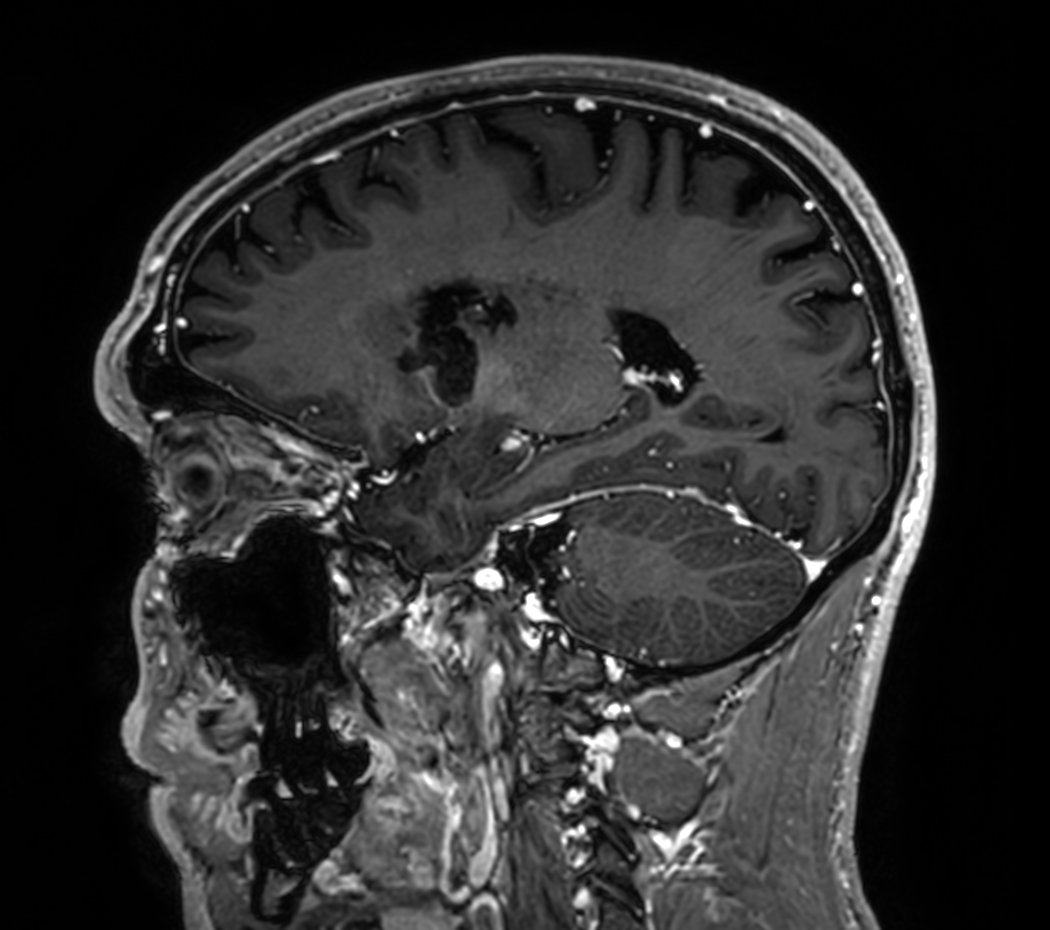

3D VIEW - T1w Black Blood